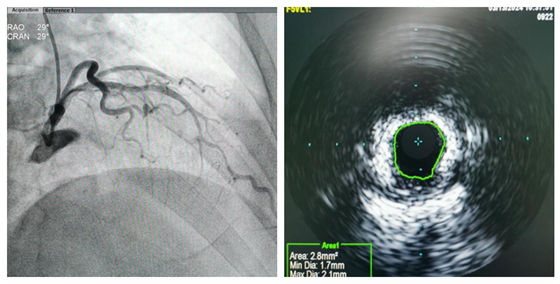

今年58岁的高大叔,5年前开始反复出现活动后胸闷气促,休息后可逐渐缓解。因症状逐渐加重,前来湘雅常德医院心血管内科门诊就诊,门诊医生了解高大叔症状,且有多年的高血压及糖尿病病史,考虑为冠心病,心绞痛。立即安排其住院,住院后完善对患者冠脉造影检查发现,前降支近-中段弥漫性狭窄30%-50%伴钙化,远段弥漫性狭窄50%-80%。进一步行IVUS检查可见前降支近段严重钙化病变,可见300°钙化。

完善术前准备后,在心血管内科主任彭道地指导下,杨国栋、龚辉、彭双携手介入团队,于前降支近中段使用乐普3.0×12mm冲击波球囊以4atm扩张,释放冲击波脉冲,共重复8个周期,然后植入3枚药物洗脱支架覆盖病变。术后复查造影示支架贴壁良好,支架内无狭窄,远端血流正常,手术顺利完成。没有出现并发症。